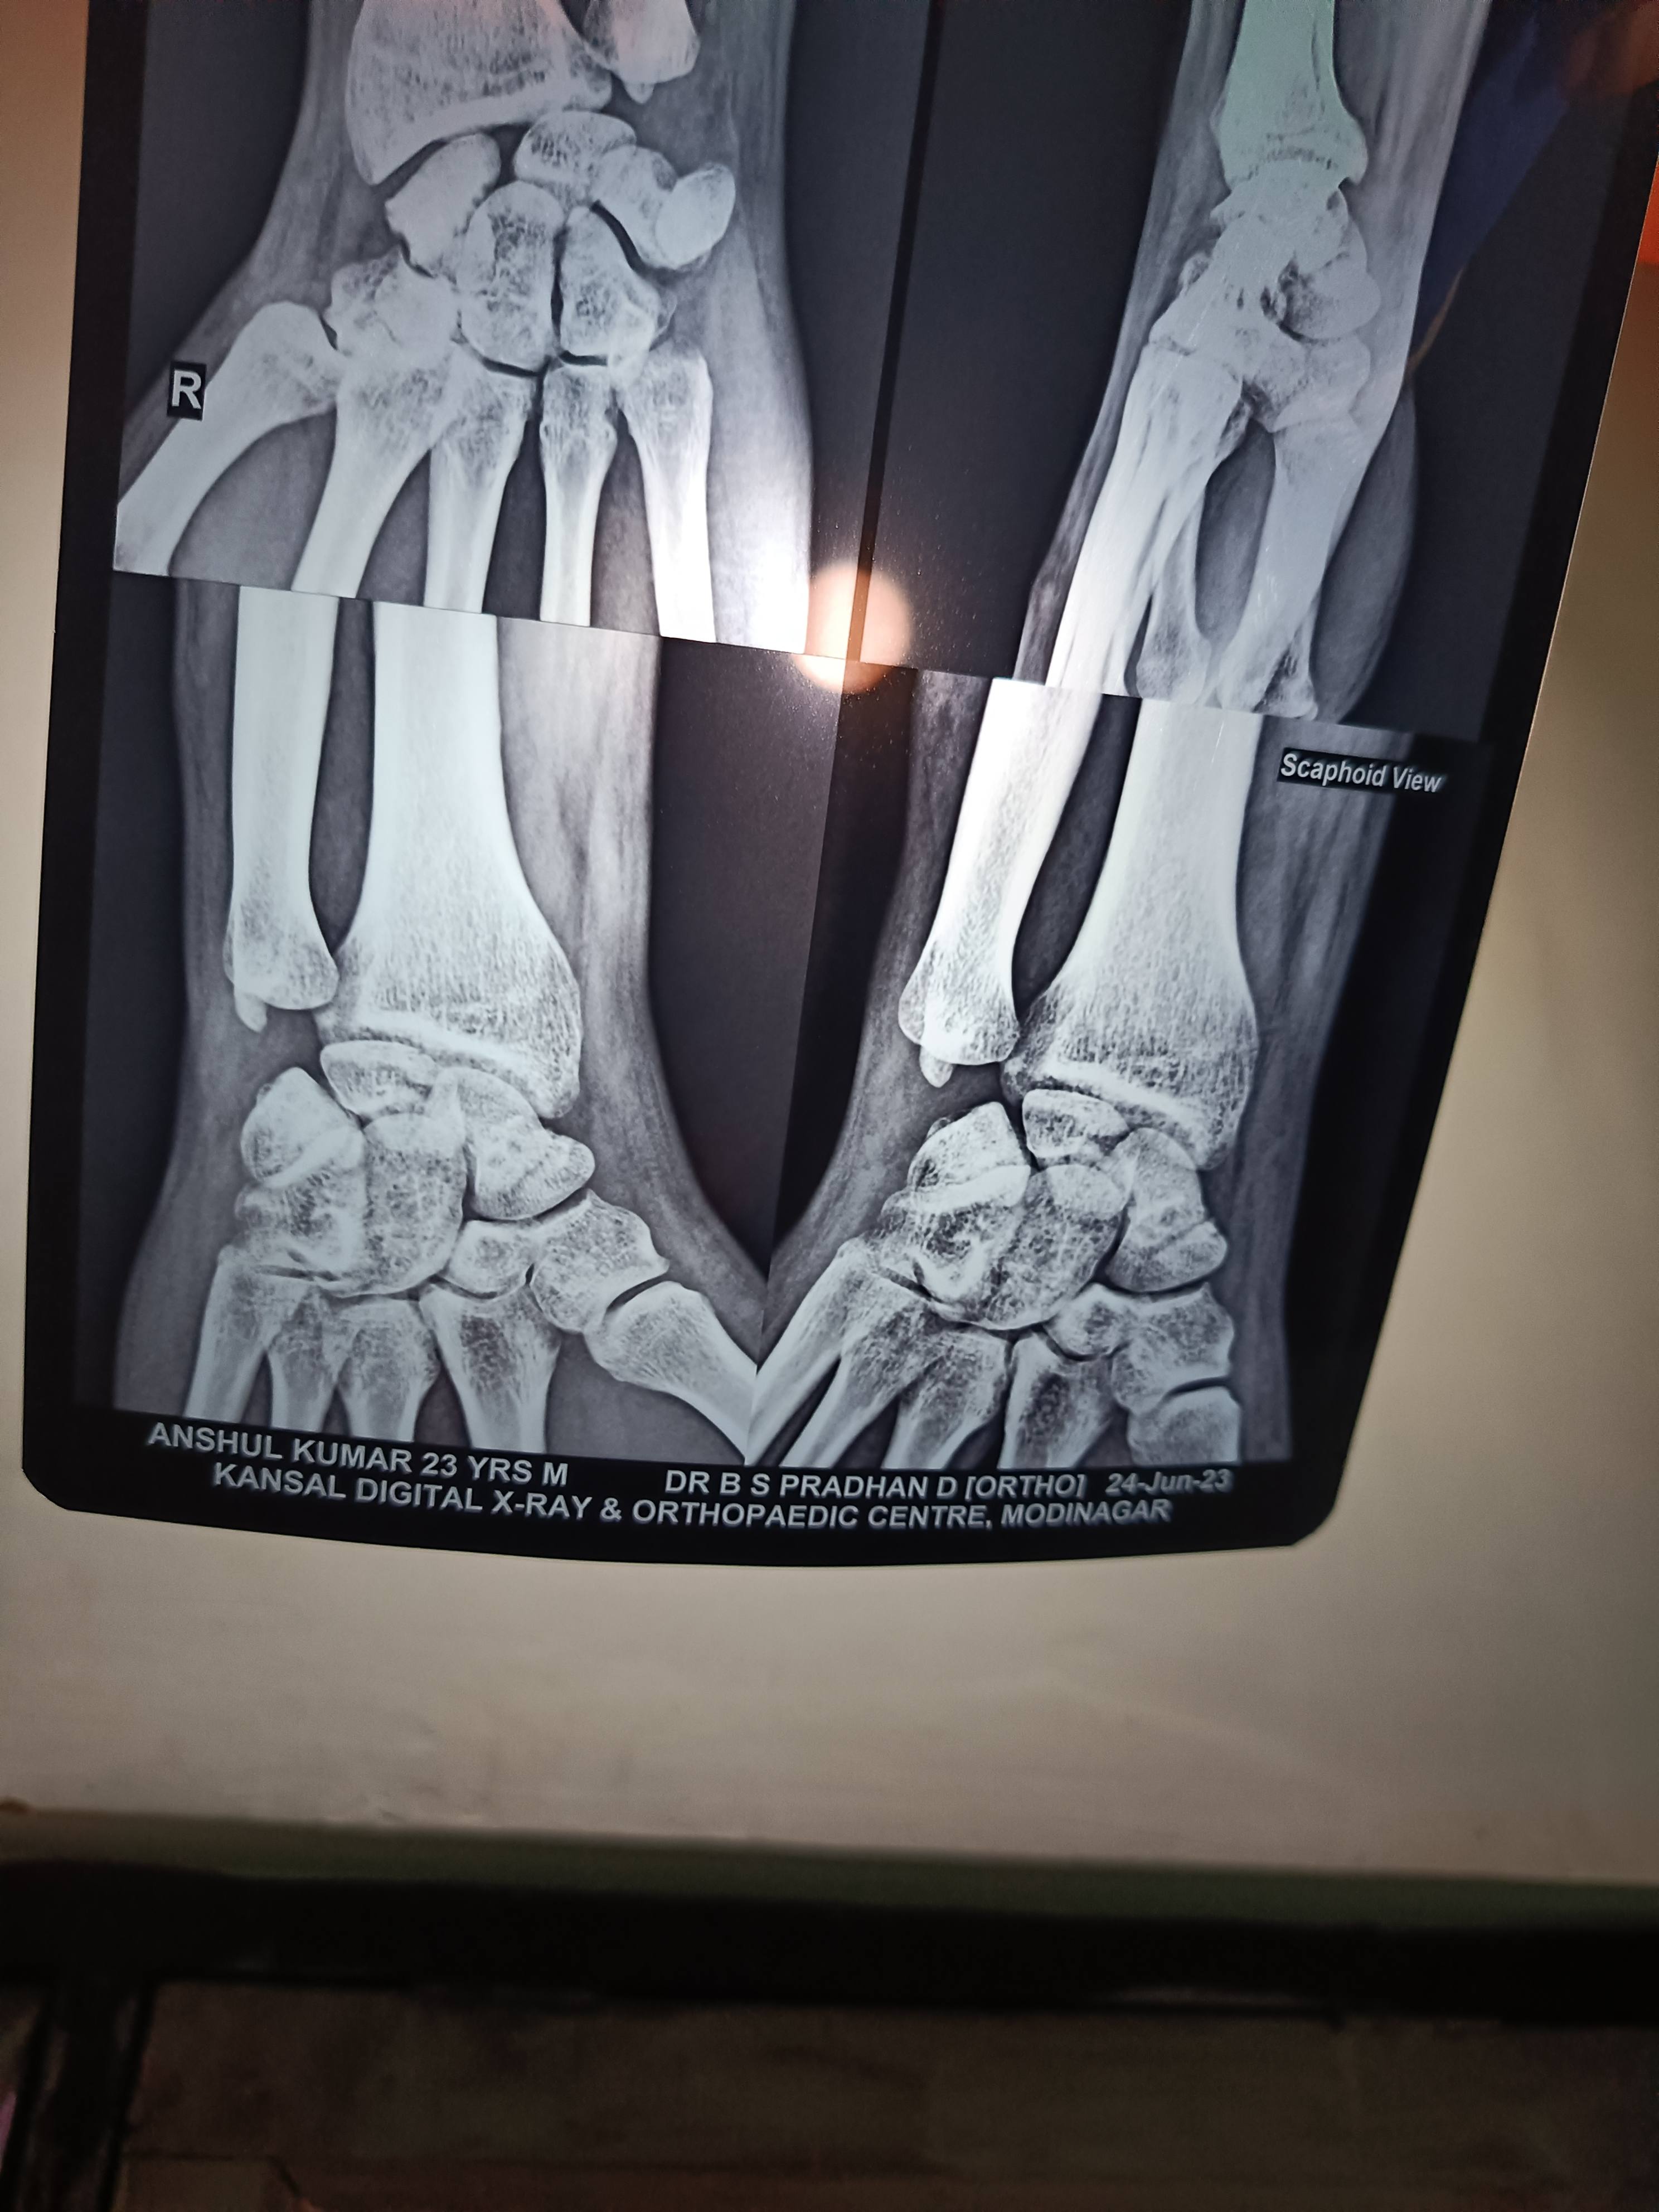

Sir 3 month pahle scaphoid fracture hua tha

Tab dhyan nahi Diya tha ab plaster kraya h

Kya plaster se sahi ho jayega ya operation karana hoga